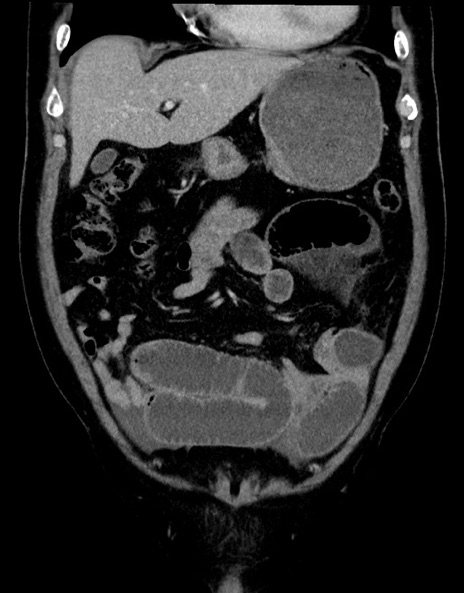

症例15(冠状断像)

【症例】70歳代男性

【主訴】腹痛

【現病歴】今朝から腹痛あり。全体的に痛い。特に左上の方。排ガスが今日はない。冷や汗が出る。

【既往歴】直腸癌術後

【身体所見】左側腹部〜上腹部に圧痛あり。腹膜刺激症状明らかなではない。軽度反跳痛。左下腹部に術後瘢痕あり。

【データ】WBC 7700、CRP 0.02

横断像